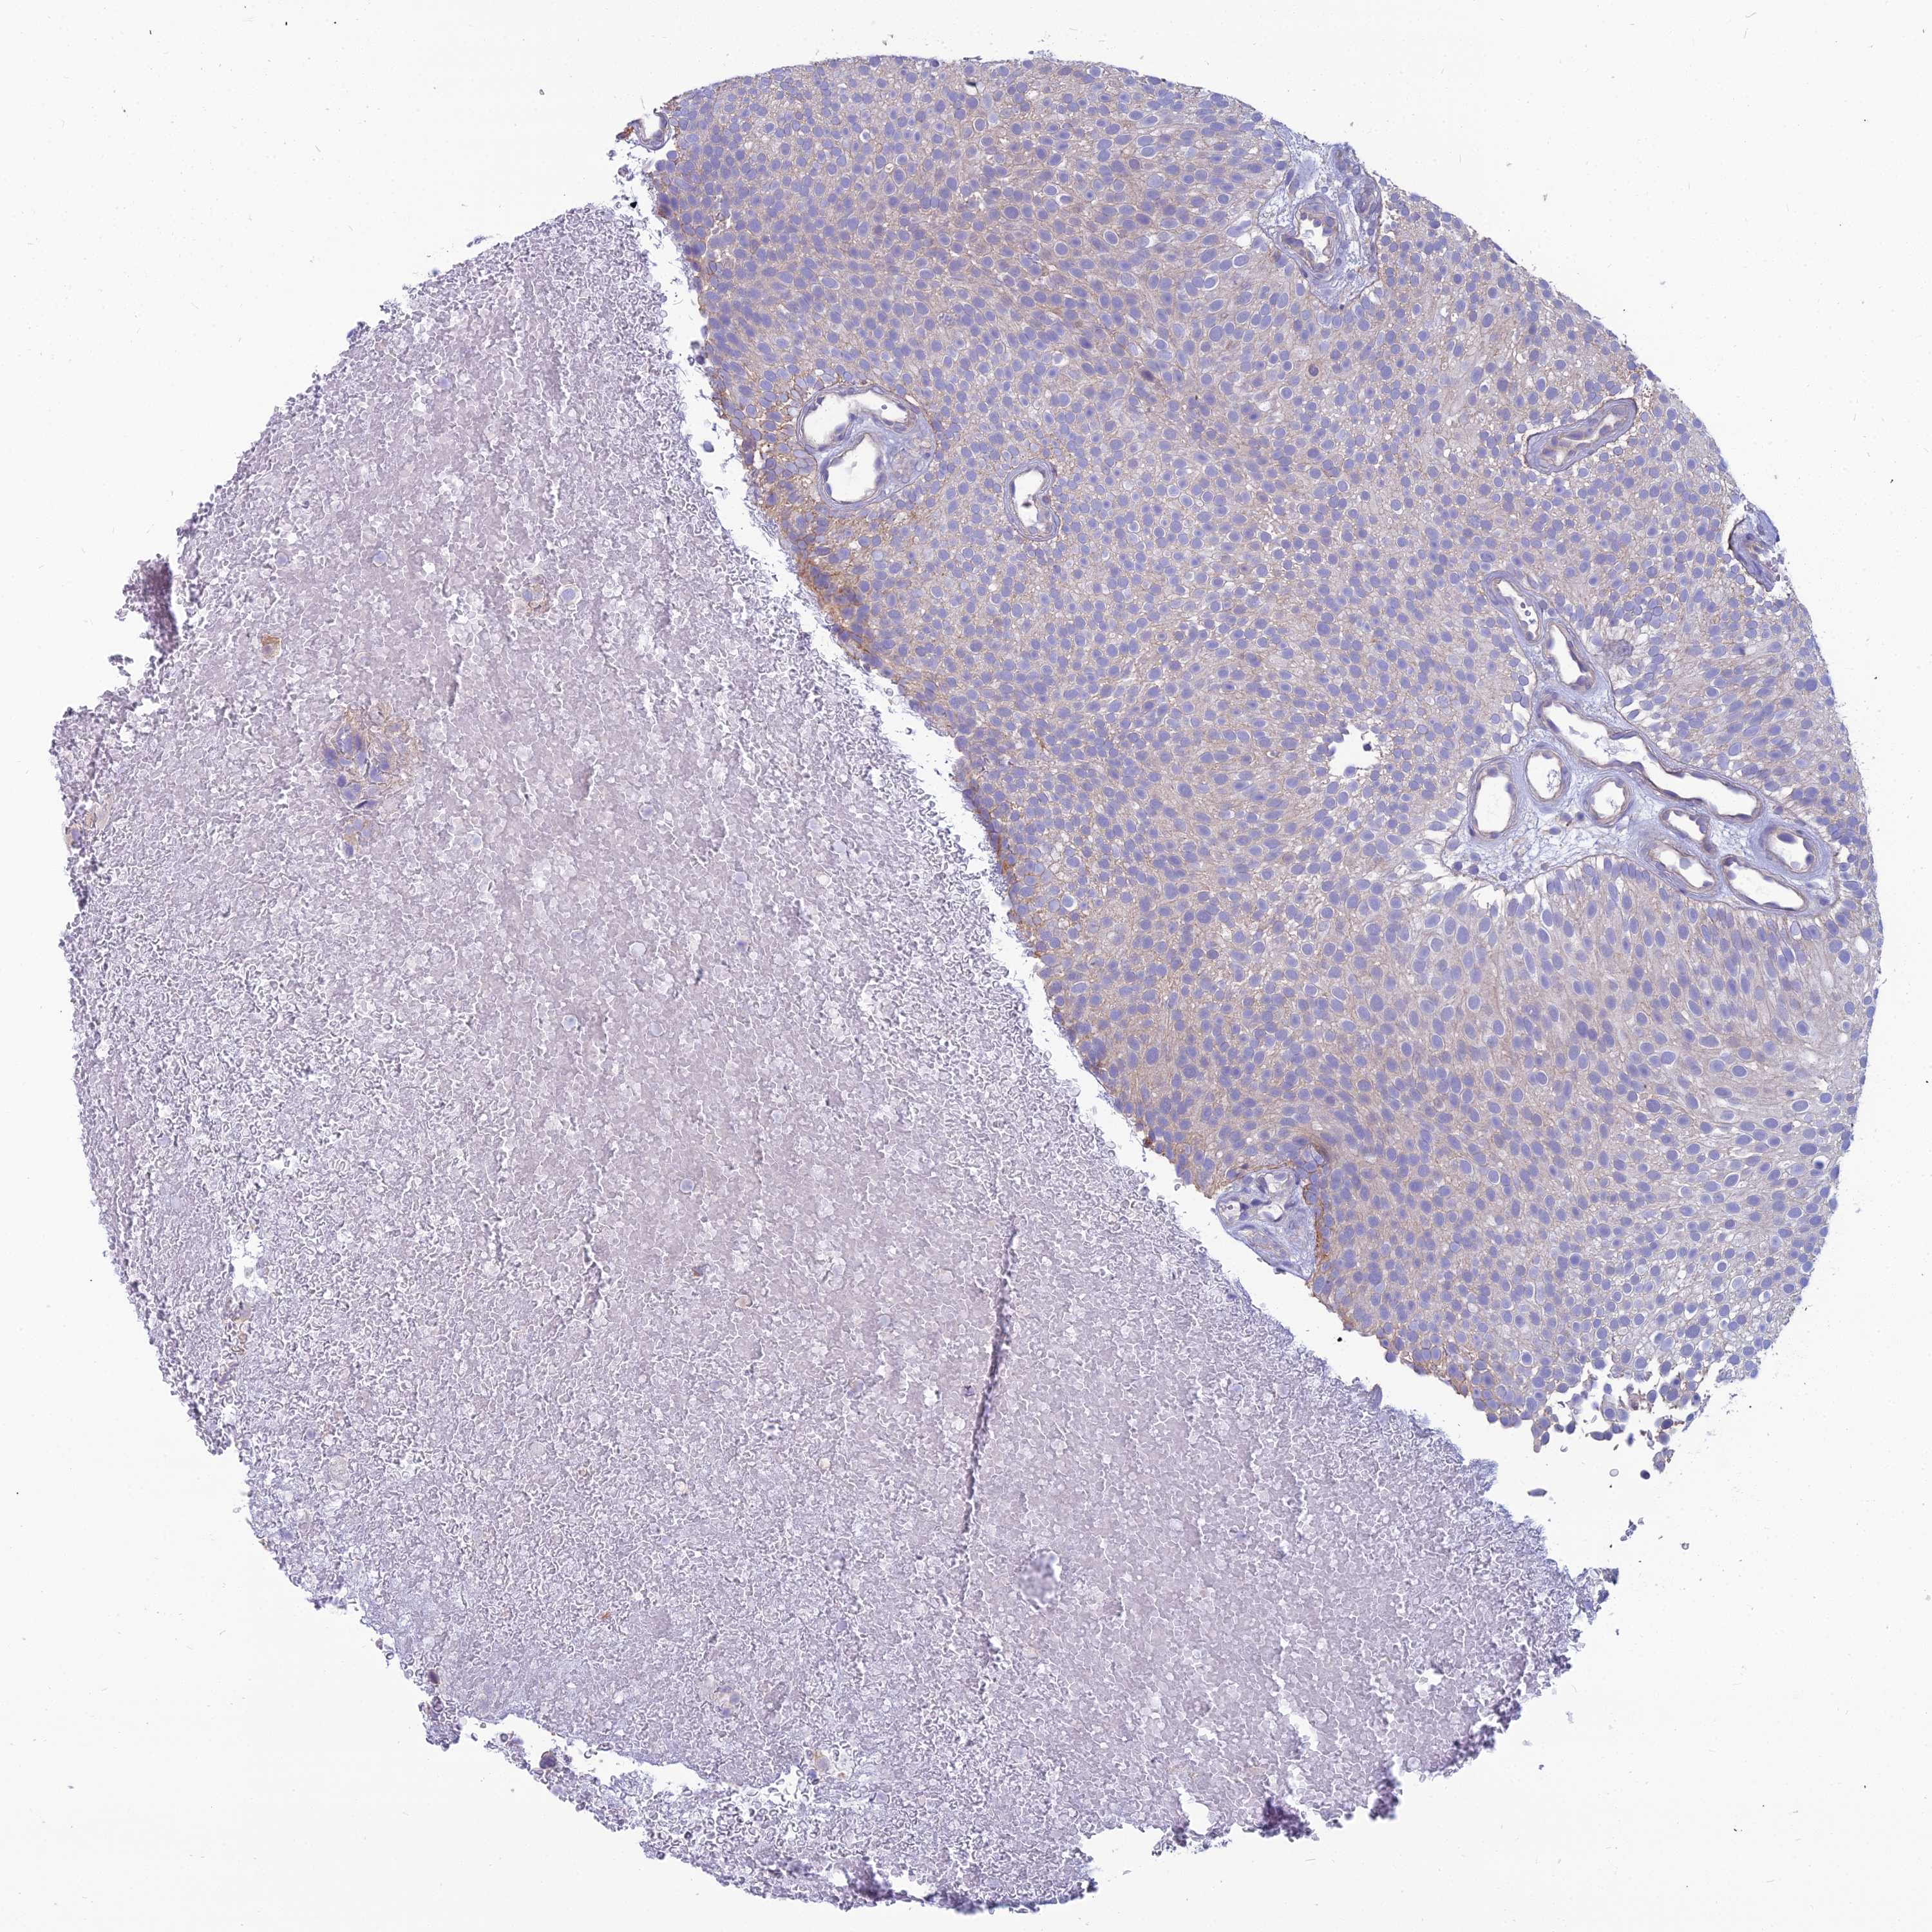

UROTHELIAL CANCER - Protein expressioni

A mouse-over function shows sample information and annotation data. Click on an image to view it in a full screen mode. Samples can be filtered based on level of antibody staining by selecting one or several of the following categories: high, medium, low and not detected. The assay and annotation is described here.

Note that samples used for immunohistochemistry by the Human Protein Atlas do not correspond to samples in the TCGA dataset.

Antibody stainingi

Antibody staining in the annotated cell types in the current human tissue is reported as not detected, low, medium, or high, based on conventional immunohistochemistry profiling in selected tissues. This score is based on the combination of the staining intensity and fraction of stained cells.

Each image is clickable and will lead to virtual microscopy that enables deeper exploration of all samples and also displays staining intensity scores, fraction scores and subcellular localization as well as patient and tissue information for each sample.

Antibody HPA041404

Antibody HPA048250

Staining

High

Medium

Low

Not detected

Intensity

Strong

Moderate

Weak

Negative

Quantity

>75%

75%-25%

<25%

None

Location

Nuclear

Cytoplasmic/membranous

Cytoplasmic/membranous,nuclear

Urothelial carcinoma, High grade

Urothelial carcinoma, Low grade